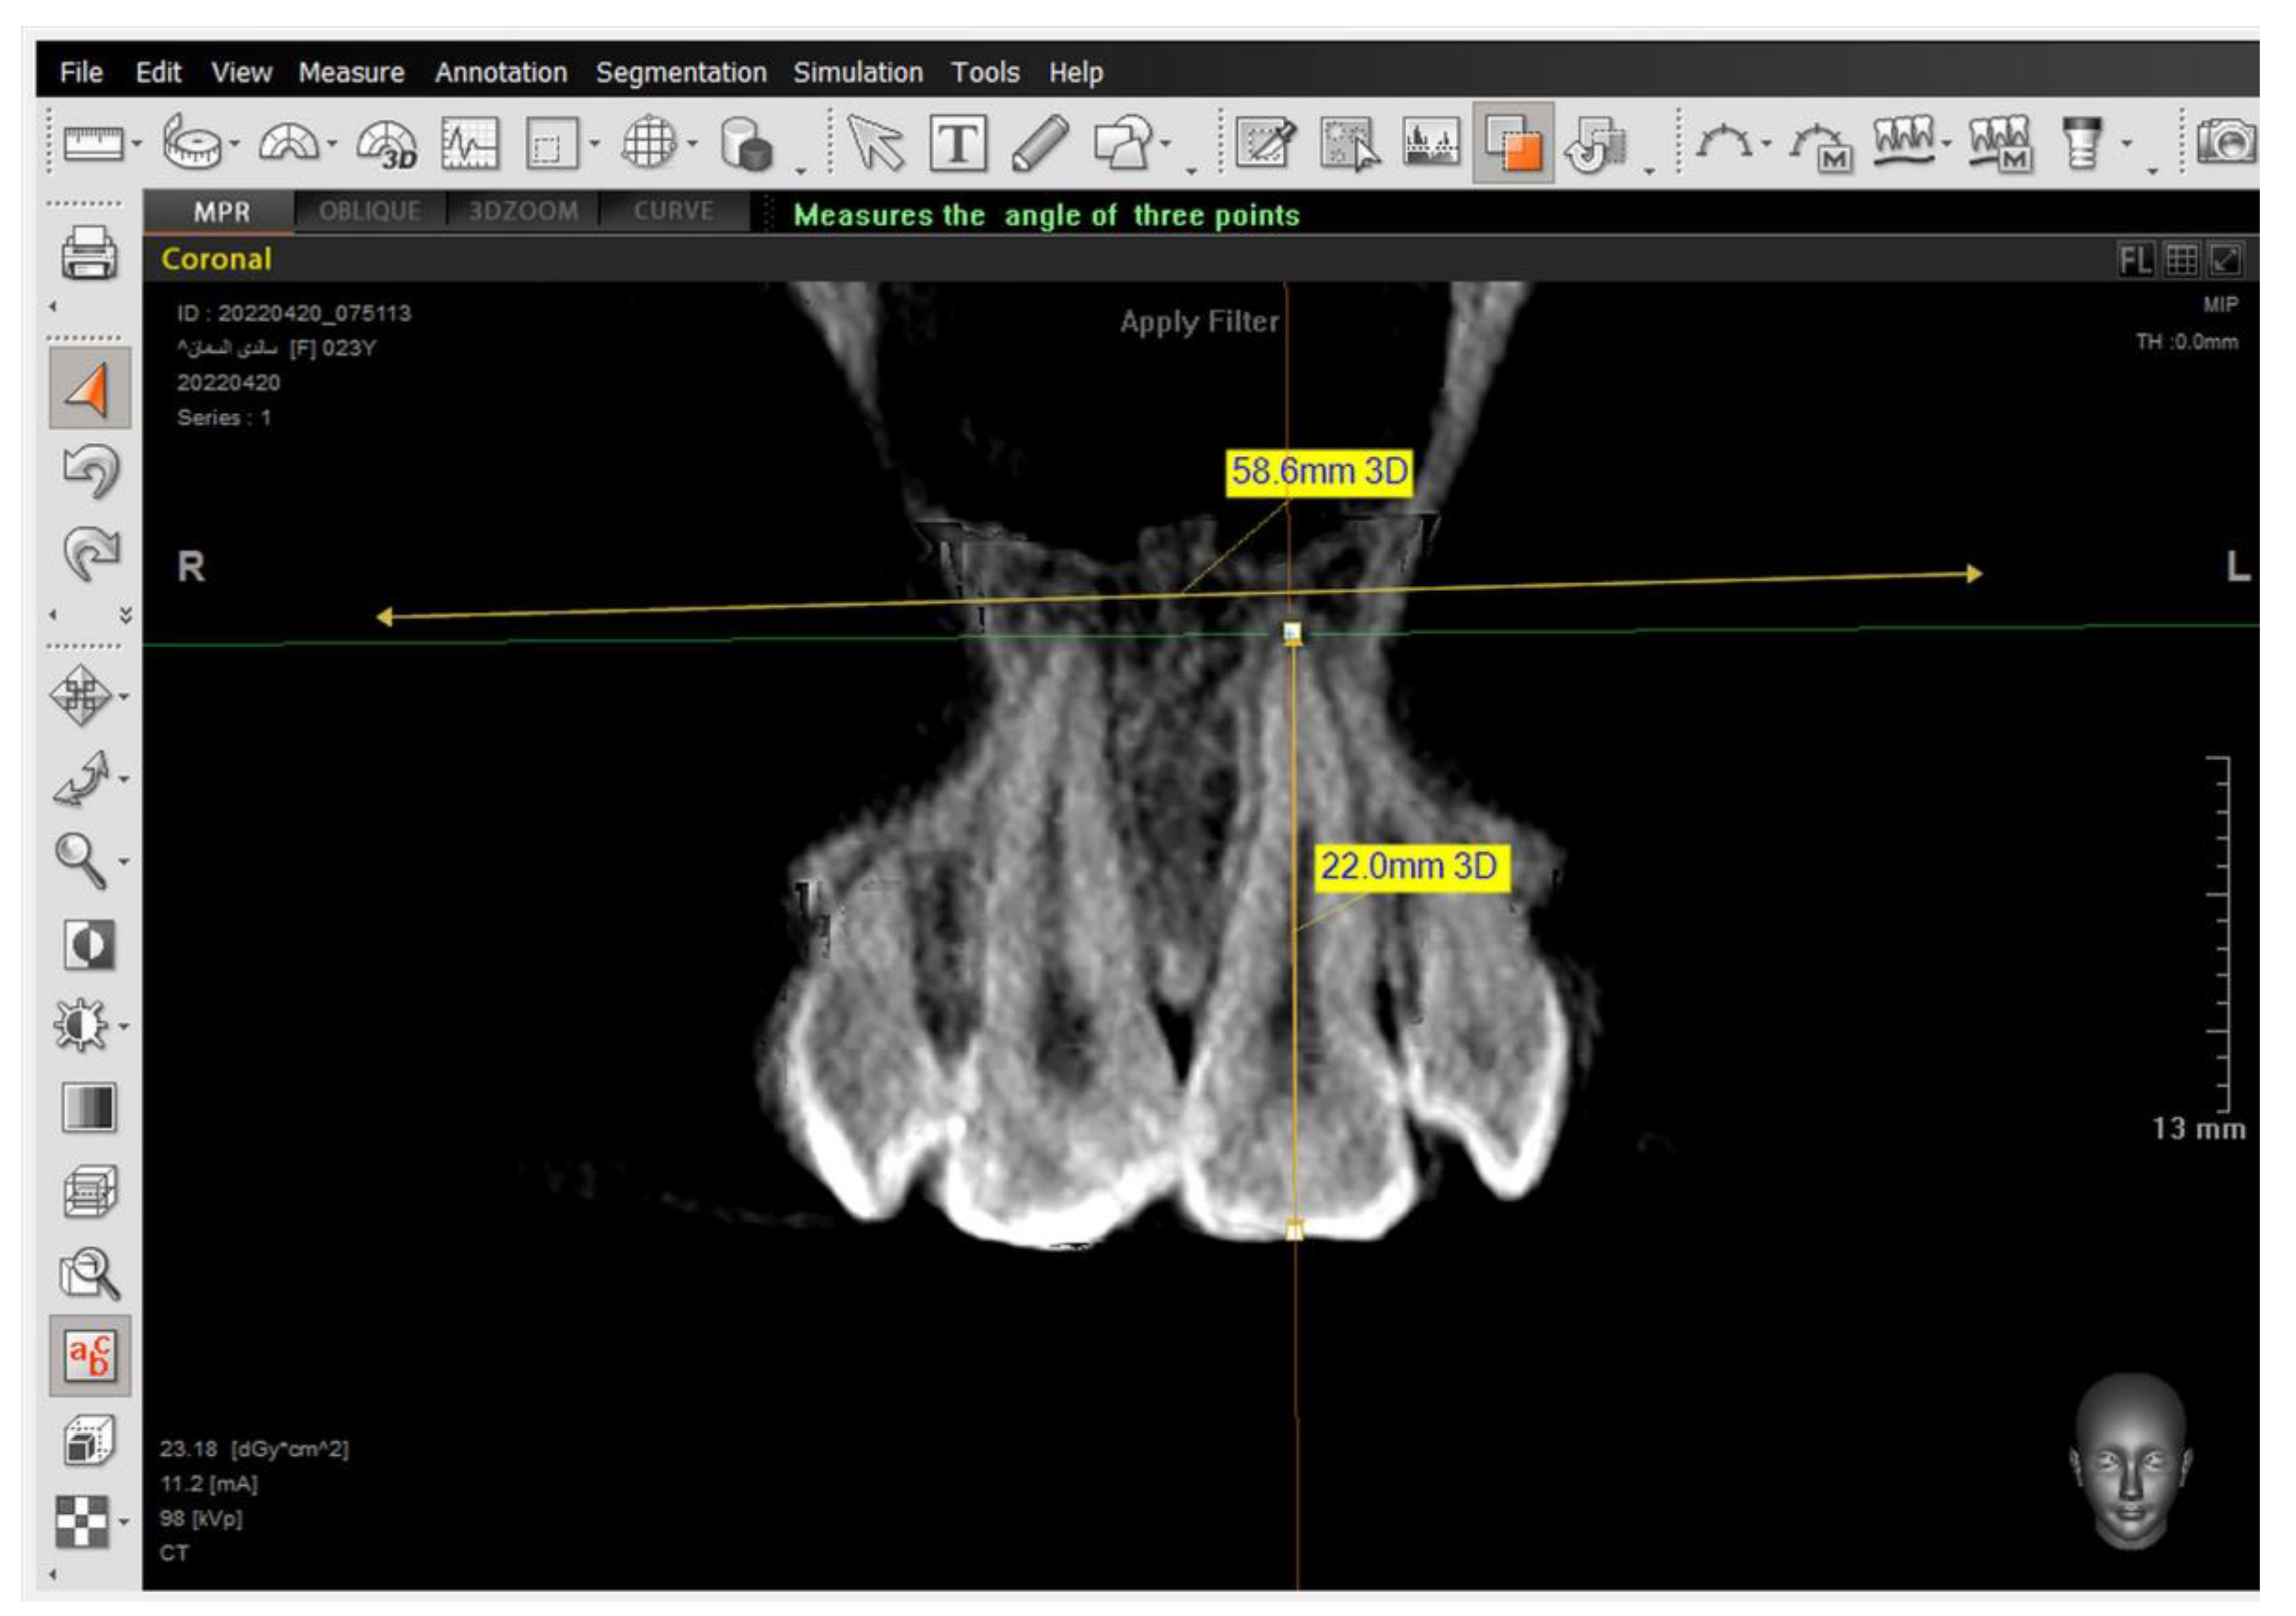

A 2D-Unsharpen filter was chosen after opening the radiograph to control the clearance of bone borders. The planes that were used and drawn were (ANS-PNS) (Go-Me) in the sagittal view, and (J-J) (Ag-Ag) in the frontal view. The green and yellow (axial and coronal plane) were moved to pass through the axis of the tooth (Figure 2 and Figure 3). Then, the orange sagittal plane in the coronal window was moved until it reached the middle of the incisal margin and the apex of the root (Figure 4). Thus, the largest buccal–lingual section of the centrals and canines was obtained in the sagittal view, referring to the buccal alveolar bone crest, detecting any bony defects (Figure 3). The definition of an alveolar defect when the cortical bone is around the vestibular surface of the root refers to the absence of at least three sequential sagittal views [8]. The defect was confirmed by 3D Zoom when the 2D reading was not clear (Figure 5) [32].

Next, a reset to the MPR (Multi-Planar Reconstruction) was performed to measure the distance between the jaw plane and the referred alveolar bone crest (Figure 6) [32].

The same steps were performed for the 2nd premolars but in different directions—in the coronal window for referring buccal alveolar ridge and dehiscence and fenestrations, and in the sagittal window for determining the tooth axis.

The presence of the dehiscence and fenestrations (Figure 5), and the distance between the buccal alveolar crest perpendicular to the reference jaw plane for centrals and canines in the sagittal view were measured (Figure 6), as well as the 2nd premolars in the coronal view in maxilla and mandible (Figure 7) at T0 and T2.

Figure 4. The determination of the long axis of the left upper central 21 in the coronal view.

Figure 6. Measuring the distance between the tip of the buccal alveolar bone crest and the maxillary plane, and measuring the angle formed between the tooth longitudinal axis and the maxillary plane in the sagittal view.

Figure 7. Setting the tip of the alveolar bone crest. Then, measuring the distance between the tip of the buccal alveolar bone crest and the maxillary plane.